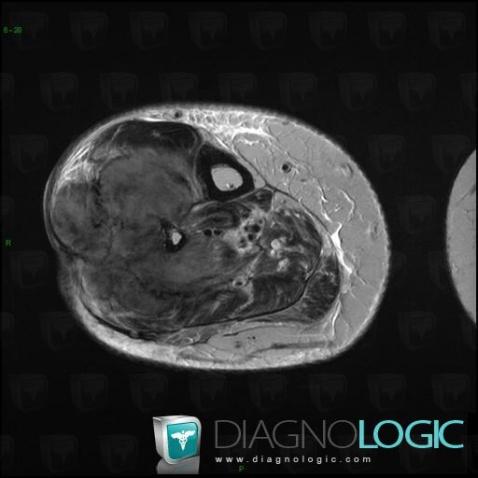

Osteosarcoma, Muscles - Leg, Other soft tissues/nerves - Leg, MRI

Here is the specific information in the key image above:

- Diagnosis Osteosarcoma, Location(s) Other soft tissues/nerves - Leg, with gamuts Hypervascular soft tissue massMuscles - Leg, with gamuts Hypervascular soft tissue mass